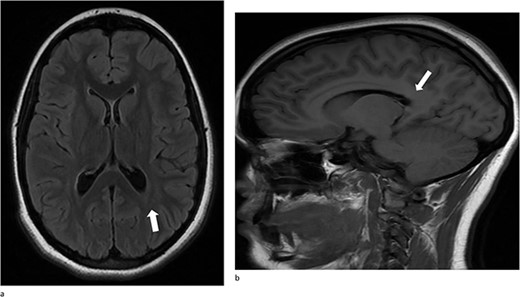

At her 12-week post-operative evaluation, follow-up MRI scans showed no residual or recurrent disease, as illustrated in Fig. 5. This patient’s genetic workup has demonstrated no propensity for neoplastic disease so far and she has resumed customary activities and routines.

(a) and (b) Stable postsurgical findings compatible with gross total resection of left atrial and adjacent periatrial tumor. No MRI evidence of residual/recurrent mass, with normal ventricular size.